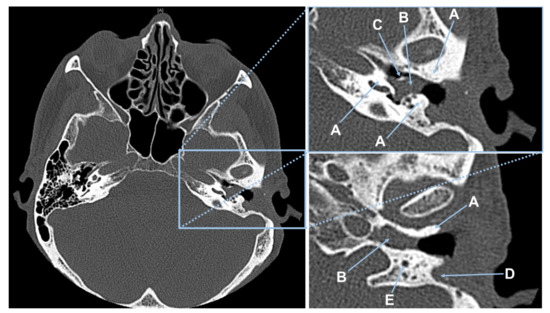

2.2. Surgical Cases and Tissue Specification